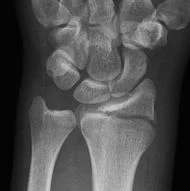

1.- Fractura de Pouteau-Colles: según este, es la lesión más común de la extremidad distal del radio. Es la fractura de la epífisis distal del radio, con desplazamiento hacia dorsal y radial. Es la más común de todas las fracturas, se observa fundamentalmente en la mujer anciana o de mediana edad, siendo la osteoporosis un factor contribuyente.

El contorno alterado de la muñeca en una fractura de Colles gravemente desplazada es evidente y se designa con “deformidad en dorso de tenedor”.